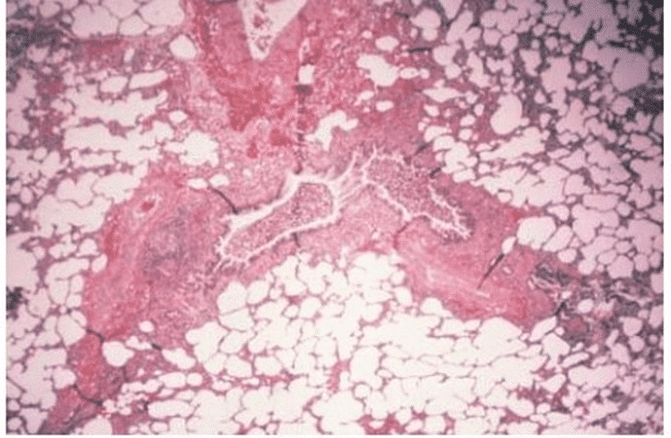

Bronchiolitis in an infant with RSV Infection. Lymphocytes infiltrate the bronchiole, and sloughed necrotic material fills and obstructs the bronchiolar lumen. The beginning of the regeneration of bronchiolar epithelium is evident